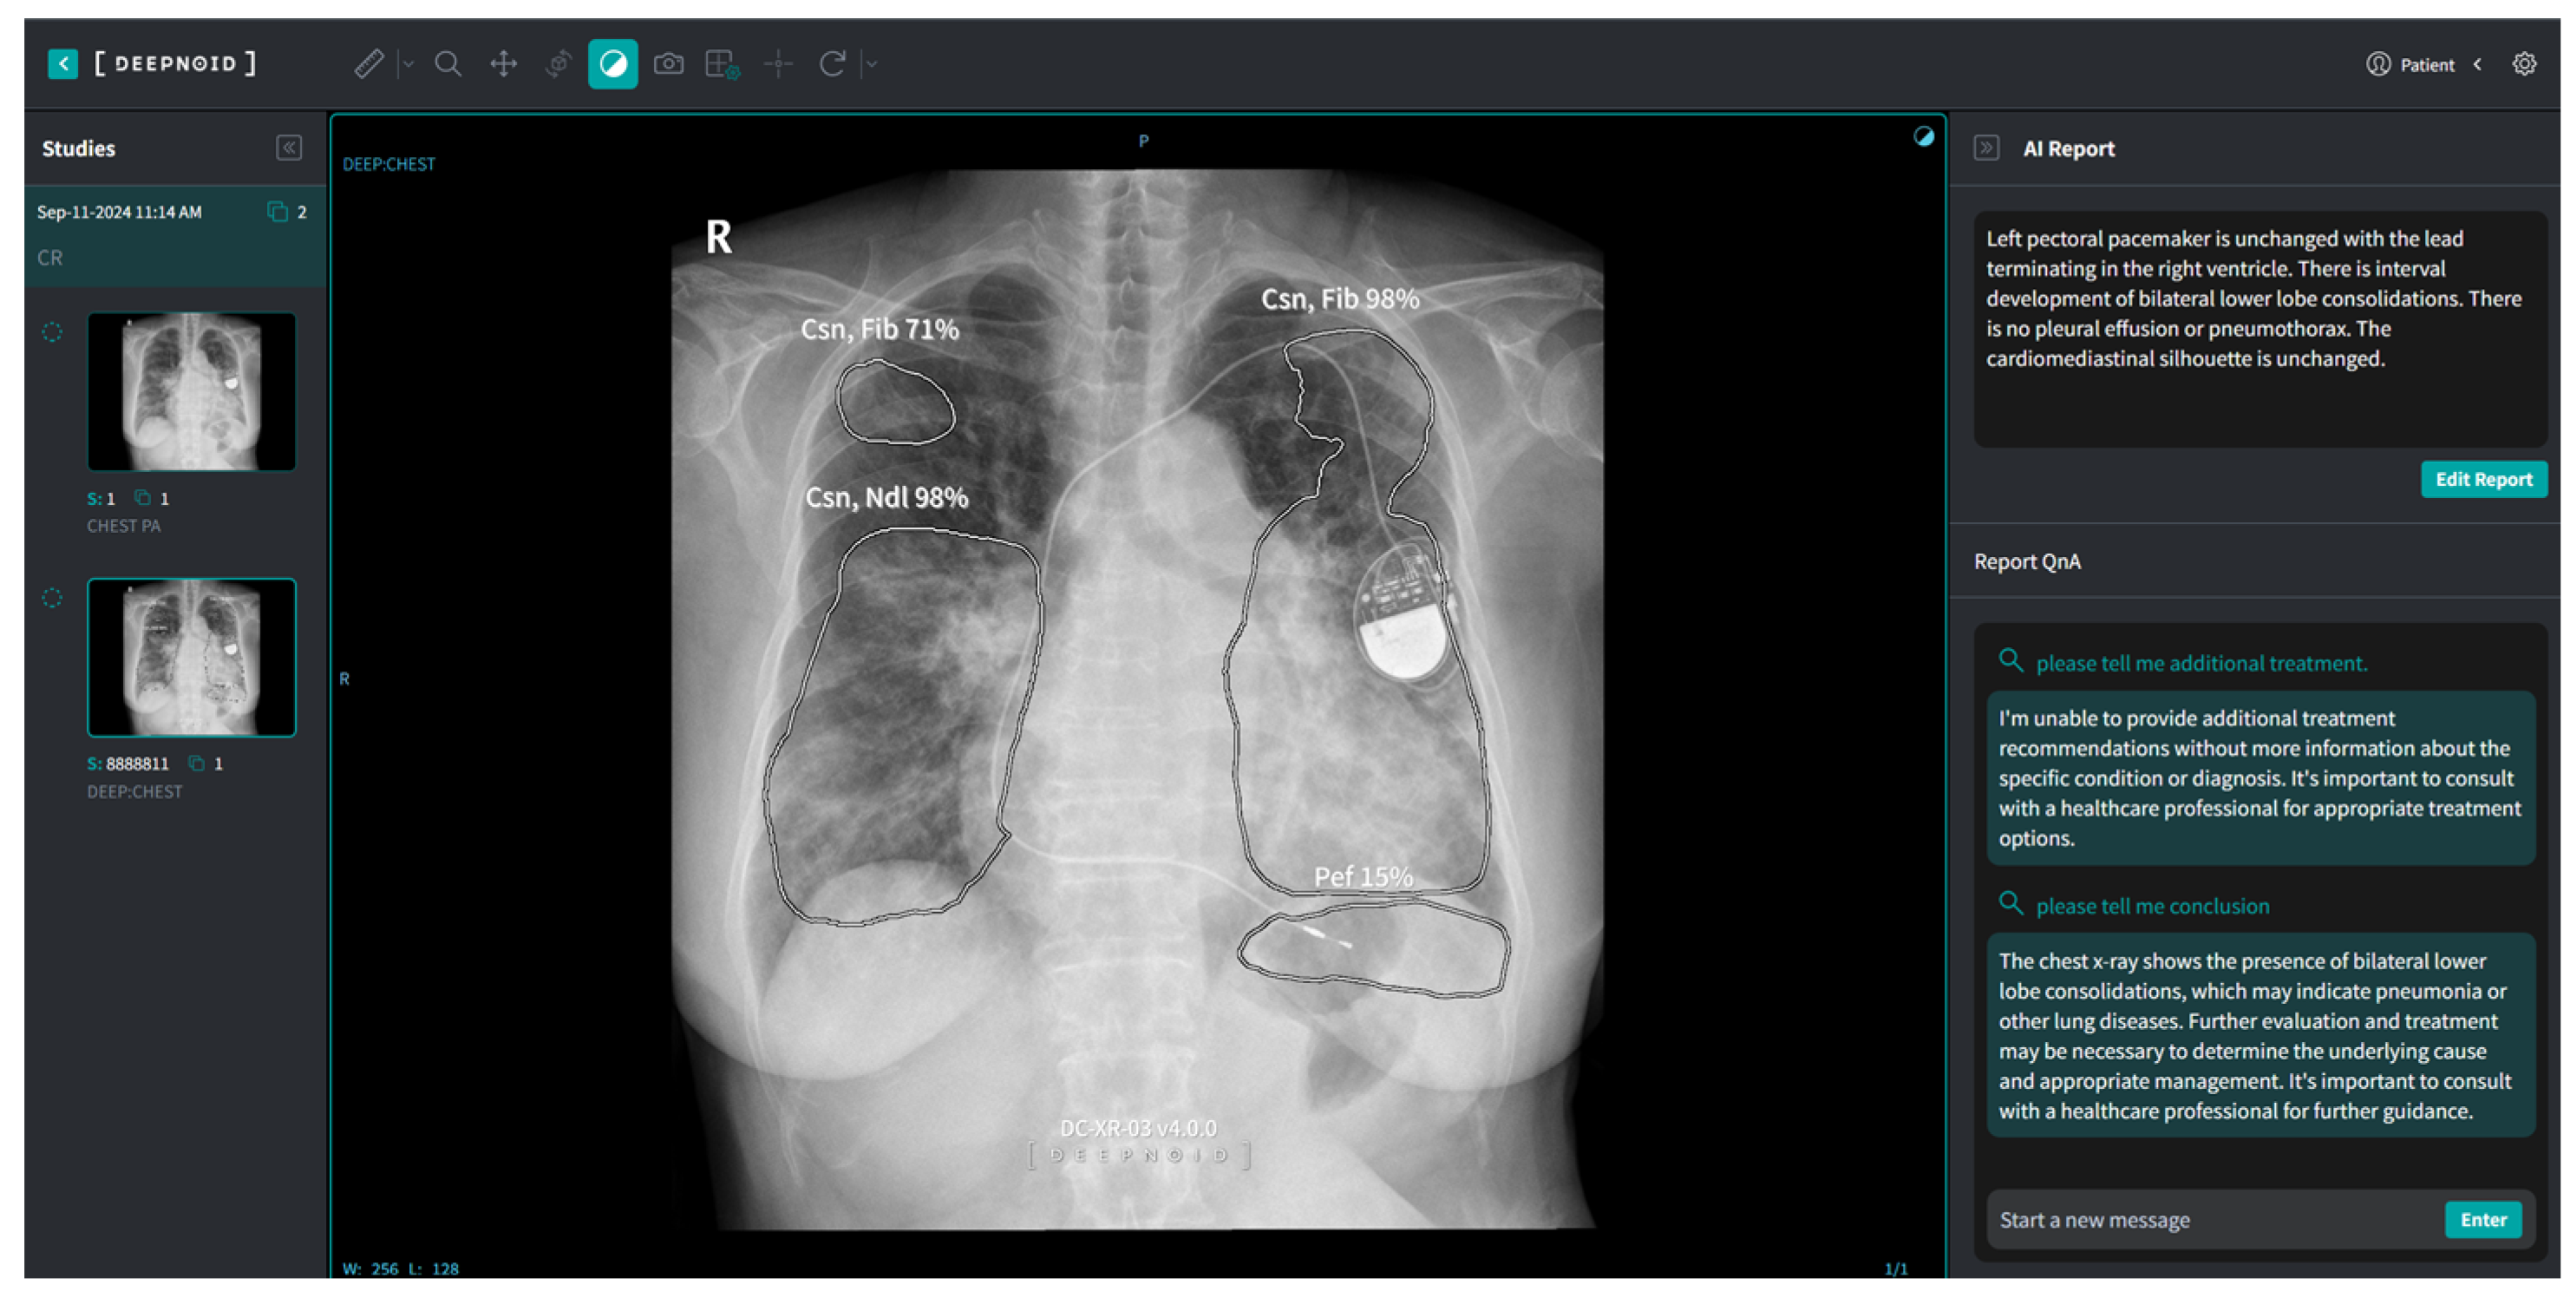

M4CXR, a cloud-based analytical platform, employs a transient data processing approach, wherein input DICOM data are immediately deleted post analysis to ensure data protection. The system generates text-based interpretations promptly upon DICOM file upload without requiring additional prompts. This study utilized a pre-release closed beta version of M4CXR (Figure 3), with public accessibility via web interface anticipated in February 2025.

Figure 3. A schematic image of M4CXR in research use.